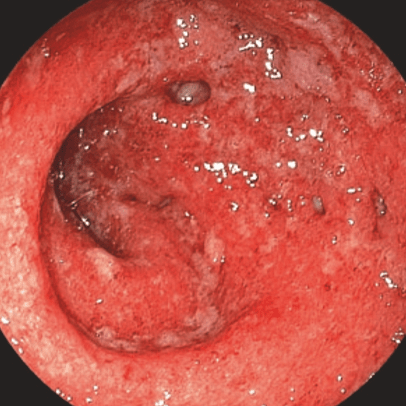

Выраженная активность воспалительного процесса:

yazvennyi_kolit.png

Выраженная активность

Гиперемия и отек

диффузные

Зернистость

выражена

Сосудистый рисунок

отсутствует

Кровоточивость

субэпителиальные геморрагии + выраженная спонтанная ранимость

Эрозии

множественные

Язвы